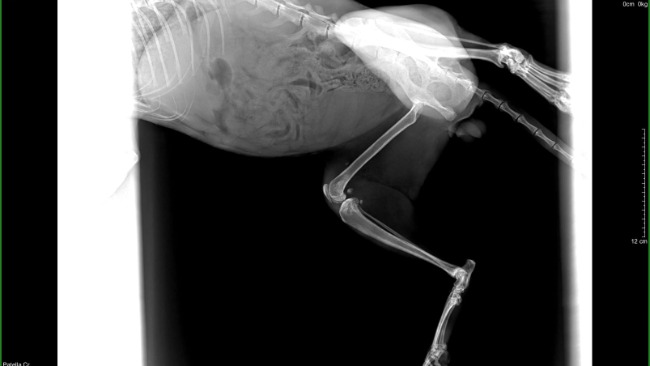

Cześć. Nazywam się Brutus. To powyżej jest moim pierwszym zdjęciem. Tam żyłem. Uszkodziłem sobie łapkę (w sumie nie sam, tylko ktoś mi pomógł). I trafiłem do weterynarza. Wyleczono mnie (koci katar) wykastrowano, jednakże z łapką mam dalej problem- zerwane więzadła. Czeka mnie operacja.. Boję się.Jestem niesamowitym miziakiem, już prawie miałem dom.. ale operacja pokrzyżowała mi plany. Musze uzbierać na zabieg. Pomożesz mi?